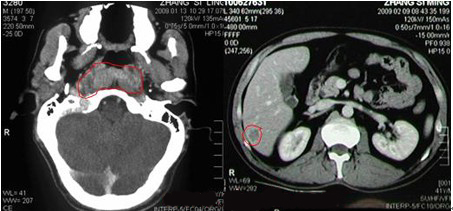

左图为确诊鼻咽癌,右图为见肝右叶转移瘤

【检查】肿块约2.1×4.4cm,质硬,固定。查鼻咽镜加病理组织活检诊断:(鼻咽部)非角化癌(分化型)。查鼻咽CT:鼻咽癌。

【诊断】鼻咽癌晚期(鼻咽癌原肝右叶转移)。